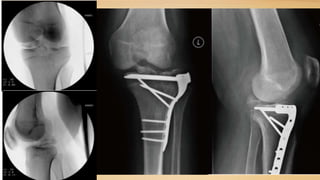

3-Lesiones multiligamentarias

asociadas a fracturas de tibia o

Las fracturas de la meseta tibial

medial se asocian con desgarros

del PLC. Las fracturas de la

meseta tibial lateral se asocian con

desgarros de MCL

Este estudio revisa el tratamiento y los resultados para dos personas de mediana edad

(≥ cincuenta años) con fracturas de la meseta tibial y multiligamentaria de rodilla

Paciente 1:

Paciente de 52 años con fx de meseta tibial y lesión completa de LCA, LCP y LCM,

tratado con fijador externo

2.5 semanas después: RAFI con placa lateral y medial, reparación de menisco externo

2.5 a 8 semanas paciente permanece inmovilizado con brace

8 semanas: empieza la fisioterapia

16 meses: deambula, valgo de 15 grados, laxitud + 3 de LCM, Lachman +1